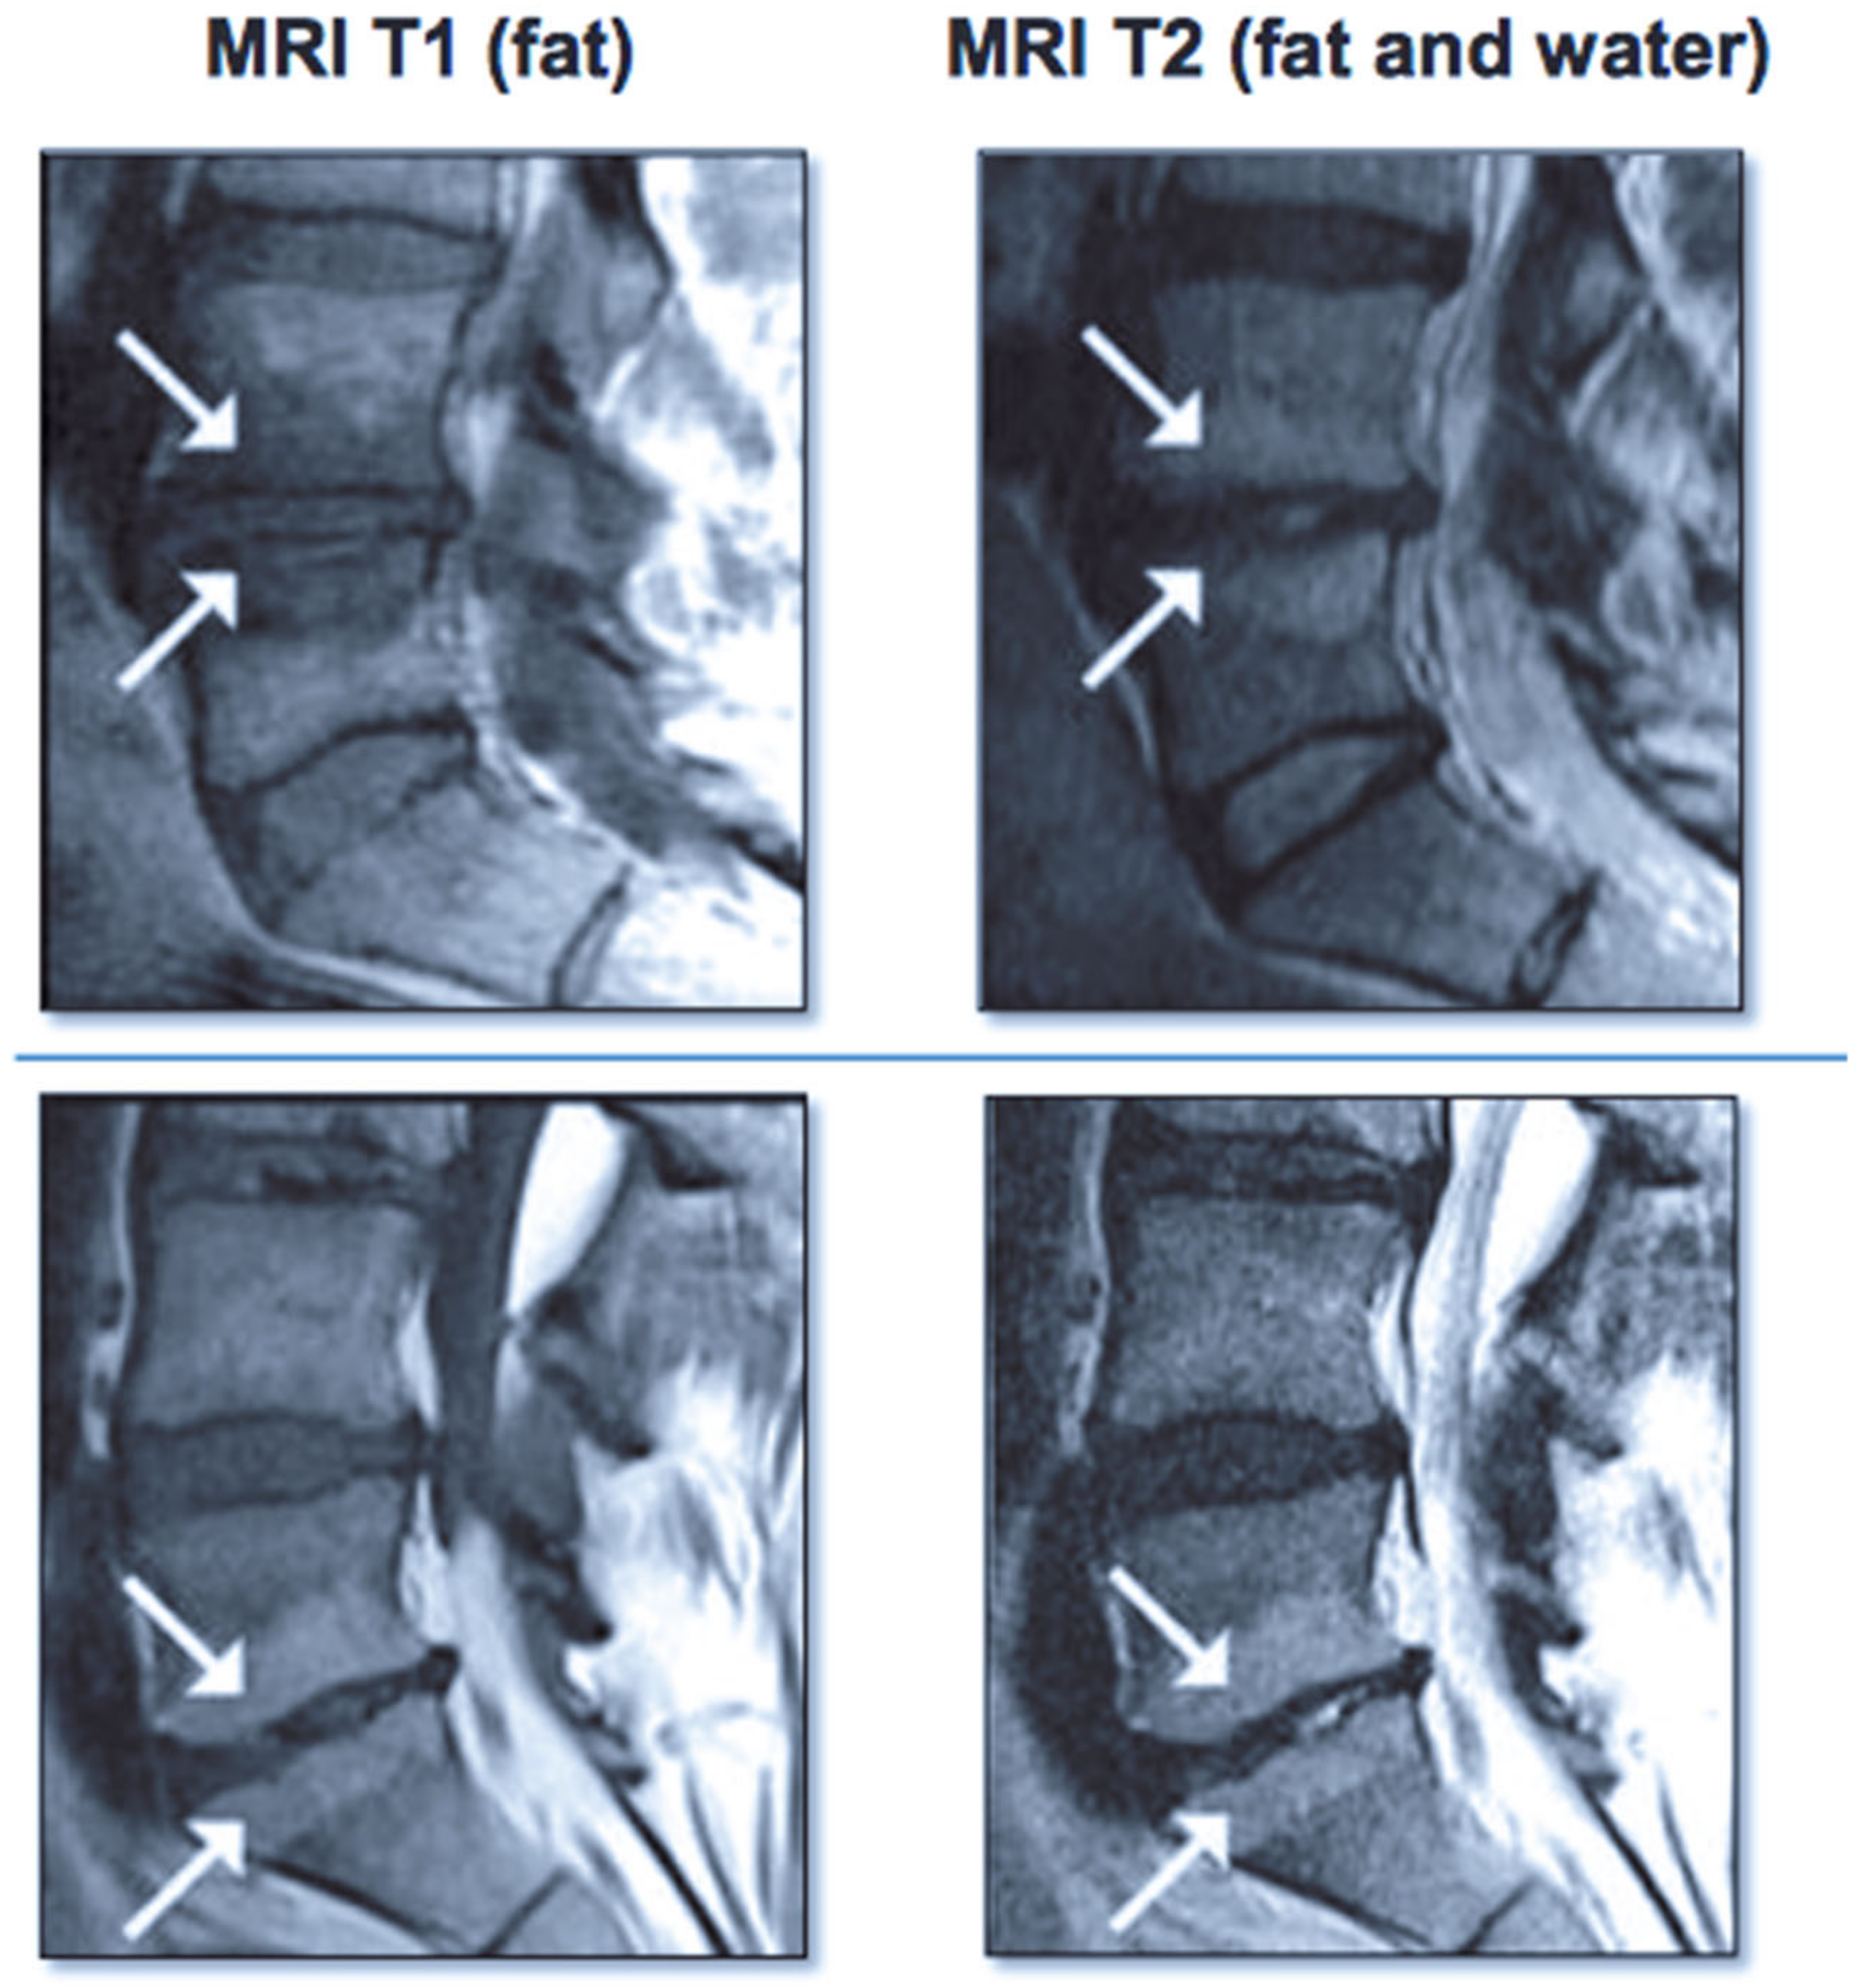

Figure 7.

Images on the left show Modic type I changes in MRI with hypo-intense T1 signal Images on the right show Modic type II changes with hyper-intense T1 and T2 signals.

Vertebrogenic pain from endplate disruption is an etiology of chronic LBP that presents clinically different from other sources. Historically, the etiology of axial lumbar spine pain has been attributed to many anatomical structures, such as intervertebral disc degeneration, spinal canal narrowing, zygapophyseal joint pain, spinal ligaments hypertrophy, muscles and nerve root inflammation, etc. However, due to limited success with interventions targeting these structures, a recent shift in the vertebral pain treatment paradigm towards vertebral endplates has emerged. The basivertebral nerve (BVN) carries nociceptive input from damaged vertebral endplates related to inflammatory cytokines, substance p, and calcitonin gene-related peptide (CGRP), histologically confirmed with protein gene product (PGP) 9.5 positive staining under microscopy [111,112]. The BVN is a branch of the sinuvertebral nerve that enters the vertebral body and travels posterior-to-anterior to a bifurcation point about 50% into the vertebral body and divides cranially and caudally towards the endplates [113,114]. Basivertebral nerve ablation (BVNA) is a minimally invasive surgical treatment of vertebral pain performed similarly to vertebral augmentation and lumbar radiofrequency ablation, in the sense that it uses a transpedicular approach to the BVN bifurcation and delivers a high-frequency ablative lesion to interrupt nociceptive signaling from injured vertebral endplates (Figure 6) [115,116]. Vertebral endplates are highly vascularized structures that are particularly susceptible to post-traumatic degeneration, fissuring, intraosseous edema, and inflammatory changes [111,112,117,118,119]. These vertebral endplate changes have a specific phenotypic marker on MRI that directly correlates to vertebrogenic pain, known as Modic changes (MCs) type 1, type 2, and type 3 (Figure 7). Type 1 MCs manifest as the decreased signal intensity of fibrovascular intraosseous bone marrow edema on T1-weighted MRI sequences and as hyperintense or increased signal intensity on T2-weighted MRI sequences. Type 2 MCs represent fatty bone marrow infiltration and typically show an increased signal intensity in both T1 and T2 MRI sequence images in contrast to type 3 MCs that have decreased intensity in both MRI sequences [120,121,122]. Although MCs are radiological findings, their presence has been reported in up to 43% of subjects with spinal pain and is highly associated with this subset etiology [118,119,123,124]. Vertebrogenic pain from endplate damage presents clinically different than other etiologies of chronic LBP with reported painful episodes of greater duration and frequency and with significant functional impairment and disability compared to other etiologies. Pain tends to be axial and progressive in nature, aggravated by sitting, standing and spinal flexion and without radicular symptoms, numbness, tingling or motor weakness. This subset population tends to respond poorly to conservative treatment, epidural steroid injections, facet joint blocks and spinal surgery [112,118,119,121,123,124,125,126,127,128,129,130,131].